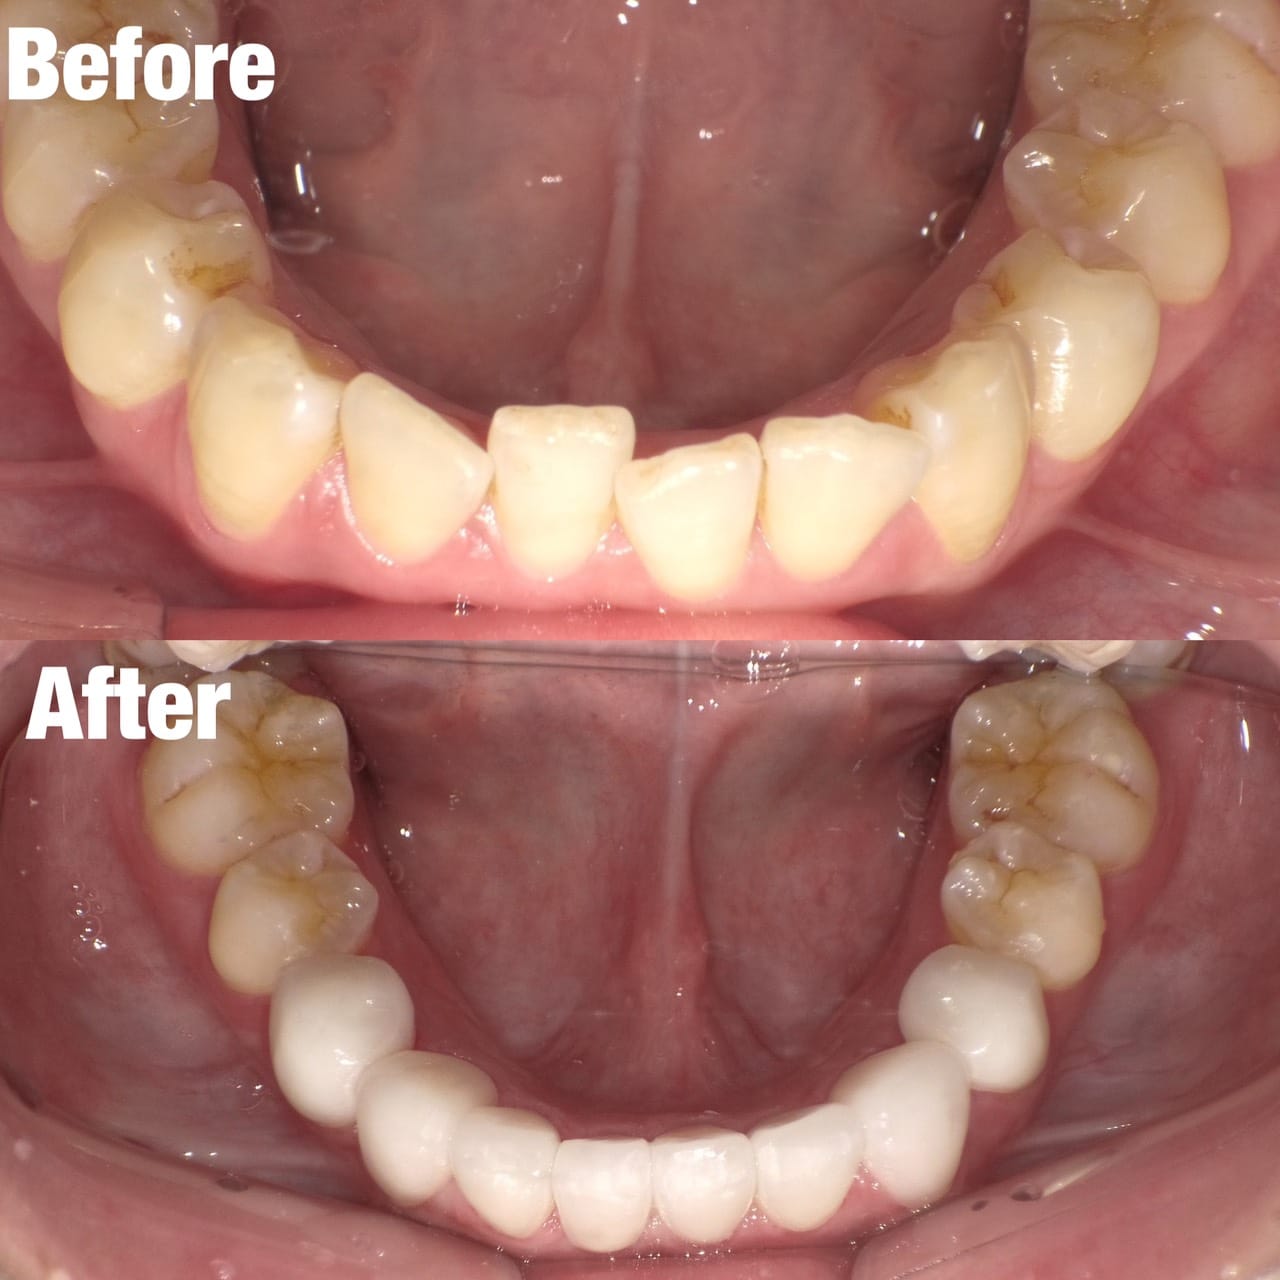

Case008

前医でマウスピース矯正を試してみたものの上手くいかず、当院にお越しくださった患者様です。

もう時間をかけたくないとの主訴だったので、マウスピース矯正ではなくセラミック矯正で治療しました。

初診時よりとても綺麗になり、満足して頂けました。

クリーニング+セラミック矯正+ホワイトニング

来院回数 3回(初回のカウンセリング含む)

担当:理事長 佐藤悠野

かぶせもの:セラミック

治療費:687,500円(エアフロー+セラミック矯正+ホワイトニング)